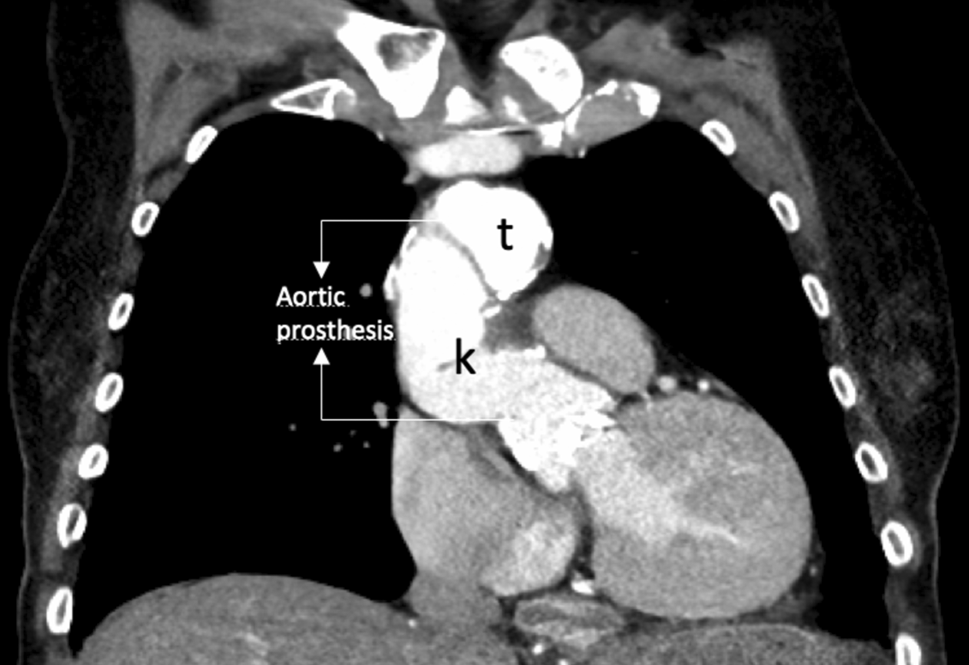

A computed tomography angiogram (CT-A) scan showed chronic residual dissection of the aortic root between the sinotubular junction/sinus of valsalva (Fig. 1) and the proximal end of the aortic prosthesis, which continued beyond the aortic arch (Fig. 2) into the descending aorta and iliofemoral vessels. It also showed partially dissected supraaortal branches and a partially thrombosed false lumen. Total diameter of the aortic arch was 4.5 cm, with true lumen diameter of 1.5 cm.

Fig. 2

Ascending aorta with aortic root, aortic prosthesis, and proximal aortic arch (t true lumen, k kinking of the prosthesis)